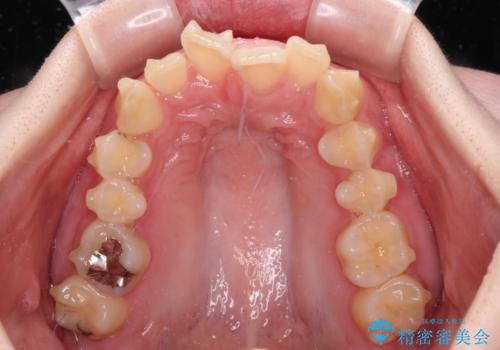

- 全体的な歯列の叢生を気にして来院された患者様です。

奥歯の咬み合わせを見ると、片方は上顎が下顎に対して相対的に前方にあり、他方は交叉した咬合の状態でした。

咬み合わせを改善するためには、上顎臼歯を後方に移動させた咬み合わせにする必要があります。

インビザライン単体で改善することも可能ですが、ディープバイトのためインビザライン単体で達成する可能性が低いと考えられたため、カリエール・ディスタライザーという補助装置を併用して、より確実性を上げることとしました。

カリエール・ディスタライザーを使用している期間、反対側はワイヤー矯正により叢生を解消していくこととしました。

奥歯の咬み合わせを改善しながら、並行してインビザラインで歯列を整えることとしました。